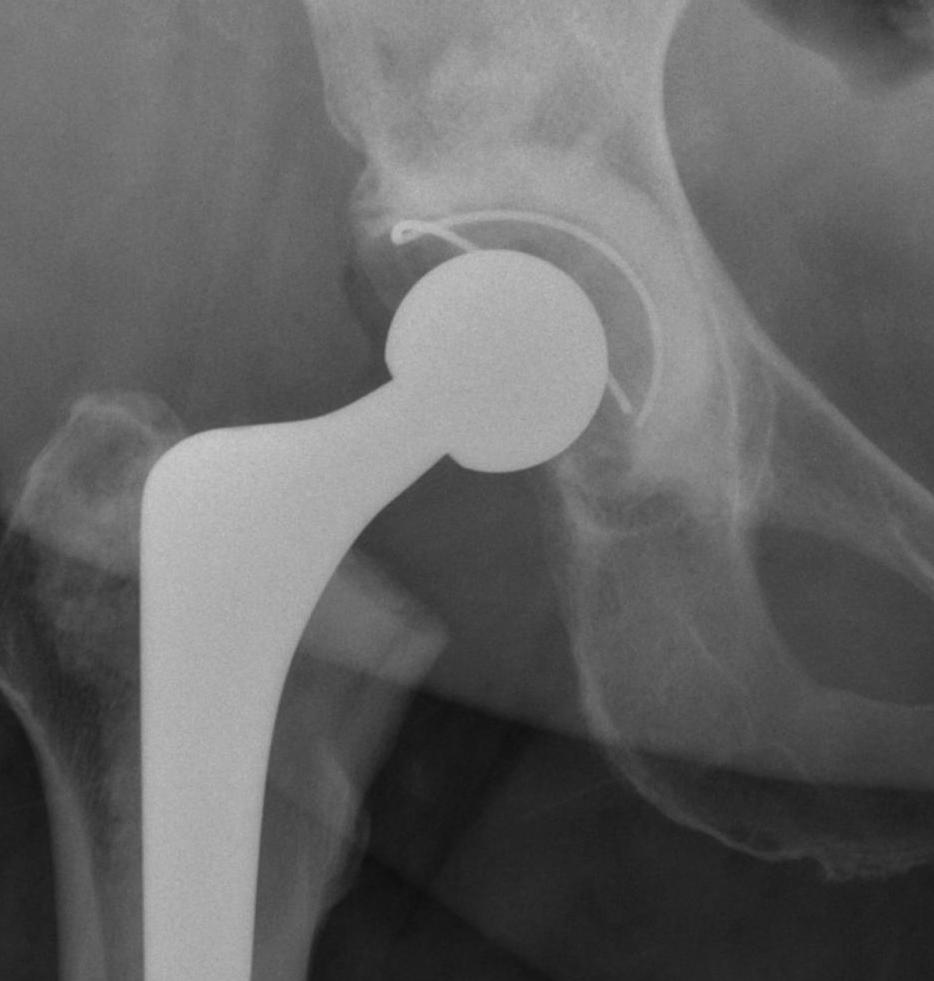

Technique cemented cup

Technique

- identify floor by removing osteophyte / reaming medially / or can use 2.5 mm drill and measure floor depth

- ream in increased sized until fits in AP diameter

- need to remove all cortical bone, can do so with smaller reamer

- many drill holes required superiorly, this is the area where good interdigitation is critical and important

- drill holes in ischium and superior pubic rami as per Charnley

- dry acetabulum with swabs and peroxide

- place reamings with spoon at inferior acetabular ligament and compress, this prevents cement leaking inferiorly

- trial cup

- can use cup with peripheral poly lip / flange to pressurise, can be cut to size

- insert ball of cement when no longer sticky

- compress till 5 minutes, twist pressuriser to remove

- dry blood with swab on a stick

- insert cup on insertion device

- place inferior cup first, medialize +++, then set closure and anteversion